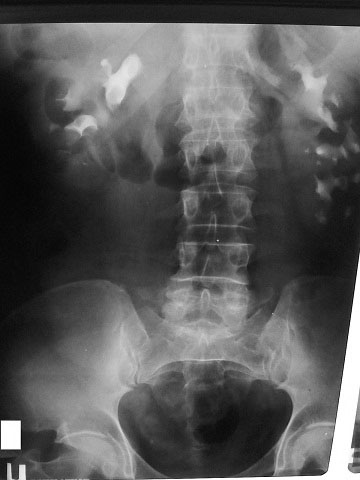

Рентгенолог сказал, что есть сдавление правого мочеточника извне на уровне с\3. Снимки не видела. Думаю, после обеда смогу их увидеть и выложить. Хочу её после обеда, как освободится аппарат, пересмотреть.

средней трети мочеточника

Сори за задержку- технические трудности.

Вот снимки: